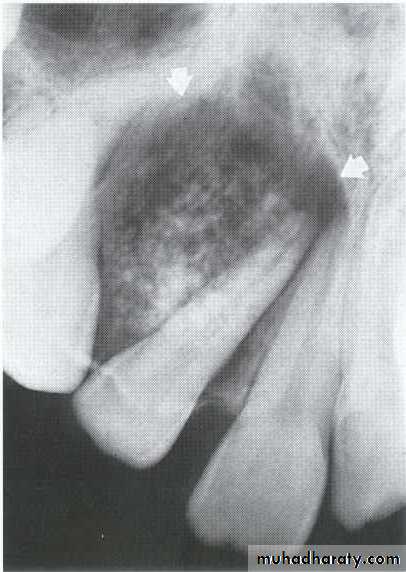

• Benign tumor appear as a solid mass, around the crown of impacted teeth.• Odontogenic Myxoma

*They are benign, intraosseous neoplasms that arise from the mesenchymal portion of the dental papilla.

*Monolucular or multiloculor radiolucency associated with missing or unerupted tooth.

*Can be distinguished from the Fibroma by histological examination(excessive ground substance myxoid tissue).

*A 55 year old man with an expansile multilocular radiolucency of the left mandible. The swelling had been noticed by the patient for approximately one year.

A: Odontogenic fibroma

B,C,D:Odontogenic myxoma.Odontogenic Adenomatoid Tumor (OAT)